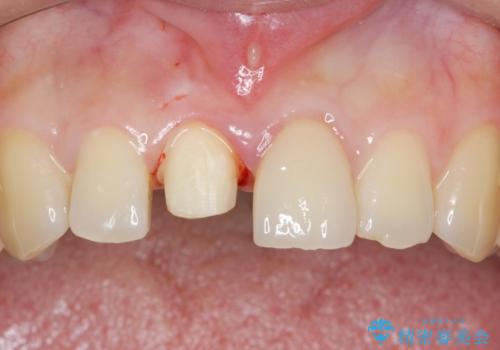

- 右上の前歯が折れたことを主訴に来院された患者様です。

歯が折れた部分は他院により応急処置で仮止めされていました。

欠けた範囲が大きかったため、セラミッククラウンによる補綴治療を行いました。